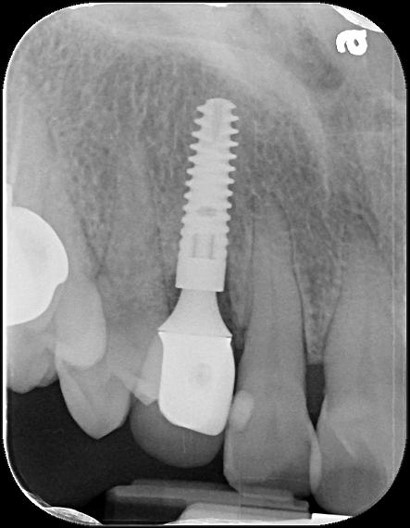

拔牙、立即植牙、補骨

植牙後,角度良好